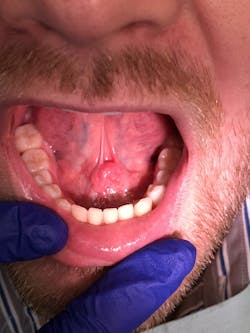

During an oral cancer screening, a soft-tissue lesion was noted on the floor of the mouth at the junction of the ventral surface of the tongue (figure 1).

The lesion was offset to the left, but appeared to cross the midline based upon the position of the frenum. The lesion was about 1.5 cm x 1 cm. Upon palpation, the tissue was firm but not indurated and mobile as one mass. The patient reported no symptoms other than mild discomfort upon palpation (figure 2). When asked about the duration of the lesion, the patient stated he had been aware of it for around two to three weeks, but it was not bothering him.